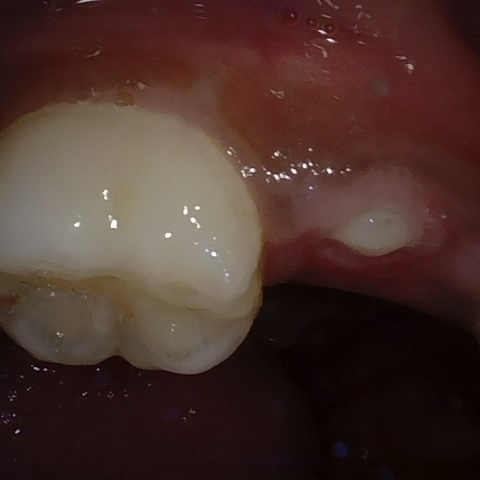

Image 361 / 1715

NHD35761

Annotated as "Good"

Original Image Rendering Image